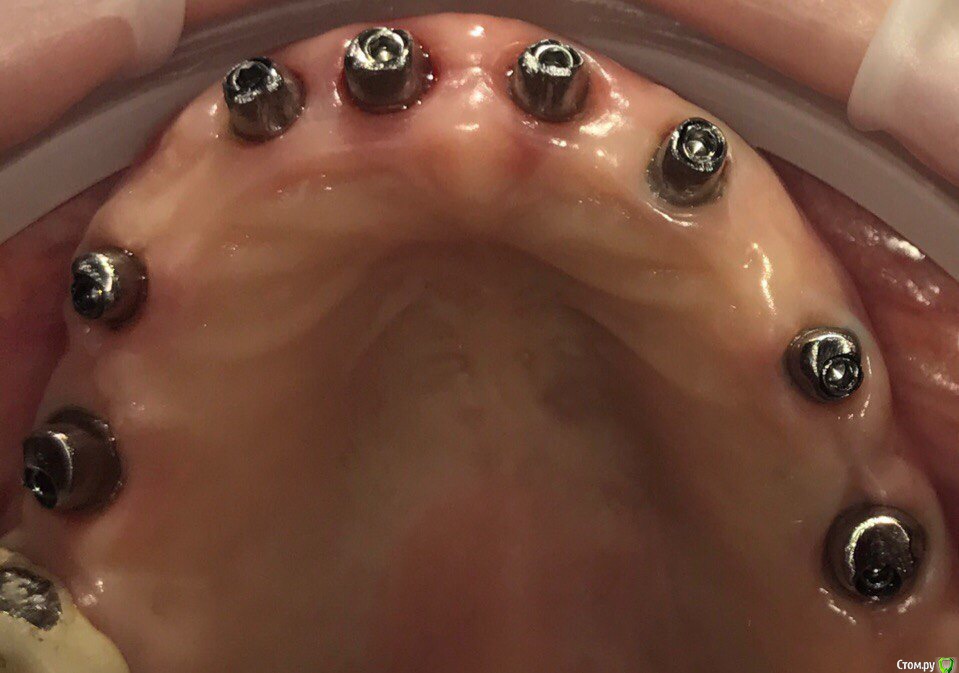

ksenistom Опубликовано 28 мая, 2017 Поделиться Опубликовано 28 мая, 2017 Уважаемые доктора,поделитесь опытом отдаленного протезирования на циркониевой дуге с цементной фиксацией,у меня сейчас сдаётся работа на титановых индивидуальных угловых абатментах,соответственно на них дуга будет фиксироваться. У меня опасения по поводу самой дуги,не будет ли сколов на ней от нагрузки в последствии?И самое страшное,как быть если раскрутится один из винтов в этой конструкции? Ссылка на комментарий

ksenistom Опубликовано 28 мая, 2017 Автор Поделиться Опубликовано 28 мая, 2017 всмысле "планирования не было"?это как так?) ну разрезали,и что дальше?зачем тут имплантаты в области центр резцов?и что за система?раз задаете такие вопросы-то получите впоследствии и сколы и раскручивание винтов абатментов,со всеми вытекающимиВ смысле,что ко мне пациент пришла когда у неё уже стояли импланты.Система дентиум. Разрезали с целью устранения баланса на дуге,по другому она не досиживалась.А чем Вам не понравились центр. импл? Ссылка на комментарий

suballex Опубликовано 29 мая, 2017 Поделиться Опубликовано 29 мая, 2017 В смысле,что ко мне пациент пришла когда у неё уже стояли импланты.Система дентиум. Разрезали с целью устранения баланса на дуге,по другому она не досиживалась.А чем Вам не понравились центр. импл?Баланс на ДЦ, это однозначное перепиливание. В смысле - новая фрезеровка. Замыкать верхнюю челюсть жестким материалом - не самая лучшая идея. Правильно боитесь. Выход - первичка из металла, вторичка - ДЦ и одиночки IPS. Или первичка из Тринии + одиночки, они и закроют шахты винтов.Кстати, тут совершенно не нужна подкова.. 1 Ссылка на комментарий